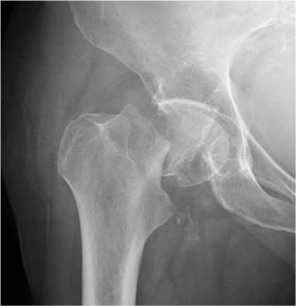

Preop Xray of an osteoporotic wrist fracture

osteoporosis

Postop xray of the fracture fixed with plate